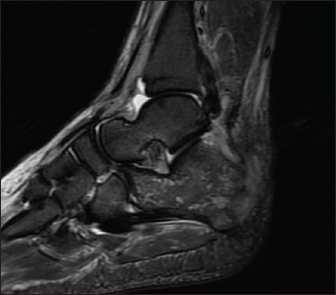

A 70-year-old male known to have diabetes mellitus presented with a 1 month history of fever and weight loss. History of multiple hospital visits and several courses of oral and intravenous antibiotics were present. Physical examination revealed hepatosplenomegaly. As he was fitting the criteria for Pyrexia of Unknown origin, work for the same was done. Routine investigations showed neutrophilic leucocytosis with raised inflammatory markers. Widal was negative. Ultrasound abdomen showed features of chronic liver disease. Contrast CT scan of abdomen showed splenic infarcts. He was started on antibiotics, but he had ongoing fever spikes. While in hospital he developed difficulty in walking due to left ankle pain. MRI foot (Fig. 1) was taken showed small intraosseous abscess in calcaneal bone. Blood cultures grew B. pseudomallei. The patient had a good recovery and was followed up in the outpatient clinic ray foot (Fig. 2) was repeated showed a resolution of osteomyelitis.

Fig. 1. MRI Rt foot—patient 1.